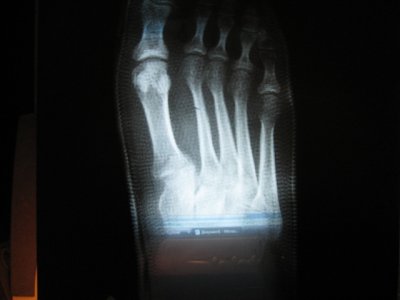

Здравствуйте!Помогите, пожалуйста. Стопу переехала машина. Сломаны 2 плюсневые кости (без смещения). В больнице положили круговую повязку (пластик) на 6 недель. Когда сняли, сделали контрольный снимок, сказали, что срастается. Но на снимке видна трещина. Можно ли считать такое срастание нормальным? Заранее спасибо.

снимки после снятия гипса: